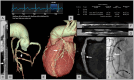

Cardiac computed tomography (CT) was introduced in the late 1990's. Since then, an increasing body of evidence on its clinical applications has rapidly emerged. From an initial emphasis on its technical efficiency and diagnostic accuracy, research around cardiac CT has now evolved towards outcomes-based studies that provide information on prognosis, safety, and cost. Thanks to the strong and compelling data generated by large, randomized control trials, the scientific societies have endorsed cardiac CT as pivotal diagnostic test for the management of appropriately selected patients with acute and chronic coronary syndrome. This consensus document endorsed by the European Association of Cardiovascular Imaging is divided into two parts and aims to provide a summary of the current evidence and to give updated indications on the appropriate use of cardiac CT in different clinical scenarios. This first part focuses on the most established applications of cardiac CT from primary prevention in asymptomatic patients, to the evaluation of patients with chronic coronary syndrome, acute chest pain, and previous coronary revascularization.